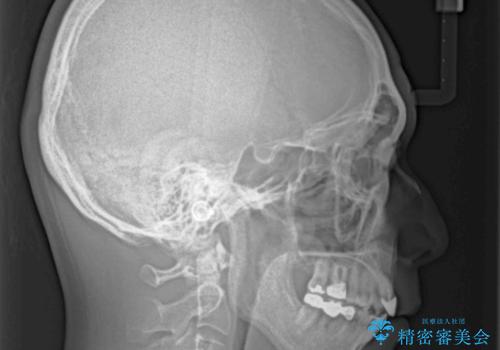

外科手術を併用した矯正治療を検討するほどに隙間の空いた開咬と、顕著な叢生が認められました。

開咬の改善には、舌の突出癖改善のためにトレーニングを行いつつ、インビザラインでの矯正治療が大変有効ですが、上顎骨が下顎骨に対して前方位に位置しており、インビザライン単独で治療を行うよりは補助装置とワイヤー矯正で奥歯の咬み合わせを改善してから、開咬改善のためのインビザライン矯正治療を行うこととしました。